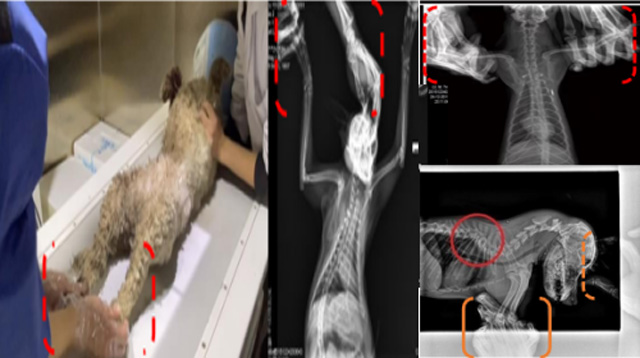

現在寵物醫療設備得到高速發展,現在有越來越多的寵物診療機構配置X射線裝置如寵物DR。寵物骨折或者有其他疾病不能通過直觀看出來的。寵物診所醫生都會使用寵物DR來做輔助檢查。但是有時候寵物醫生沒有加強防護,就在寵物DR室給寵物拍X片做檢查。這樣也是會受到X射線的輻射。因為X射線上崗是屬于職業病危害崗位。長期的輻射會對人體造成一定的危害。寵物醫生也需要接受X射線照射的上崗前都必須進行放射工作人員的職業健康體檢。體檢不合格的話是不能擔任放射工作的。未經上崗前職業健康體檢的勞動者從事接觸職業病危害作業的行為,已經違反了《中華人民共和國職業病防治法》第三十五條規定,依據《中華人民共和國職業病防治法》第七十五條規定,需要進行整改罰款。開展寵物放射診療活動,在日常工作中,對本機構的X射線危害的職業病防治,需要知道并做到以下內容:

建造X射線機房時尋找專業防護施工隊伍,對機房四方及上下方墻體進行屏蔽防護,盡可能隔室操作,使用鉛防護門并安裝工作指示燈張貼警示標識進行提醒。放射工作人員跟寵物主進入DR室需要穿戴鉛衣、鉛帽、鉛手套等做好防護,減少X射線的輻射。避免暴露在照射范圍中。寵物醫生上崗前、在崗時、離開崗位時候的職業健康體檢。如果檢查異常就需要復查跟調離放射崗位。實施個人劑量監測和防護知識培訓。并在勞動合同中向放射工作人員告知X射線危害相關內容。定期委托職業技術服務機構對機房防護、放射診療設備性能進行檢測。不能忽略了對人的保護。